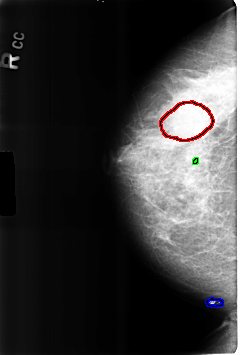

FILE: B_3226_1.RIGHT_CC.OVERLAY

TOTAL_ABNORMALITIES 3

ABNORMALITY 1

LESION_TYPE MASS SHAPE OVAL MARGINS CIRCUMSCRIBED-OBSCURED

ASSESSMENT 2

SUBTLETY 3

PATHOLOGY BENIGN

ABNORMALITY 2

LESION_TYPE CALCIFICATION TYPE COARSE DISTRIBUTION N/A

PATHOLOGY BENIGN_WITHOUT_CALLBACK

ABNORMALITY 3